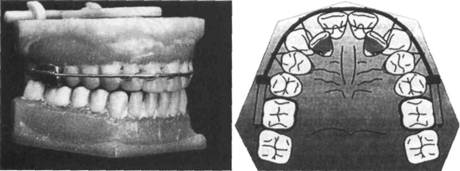

Внутриротовые несъемные аппараты. Дуга Энгля является несъемным аппаратом. Известны две ее разновидности — стационарная и скользящая. Стационарная дуга изготавливается фабрично. Она состоит из отрезка стальной нержавеющей проволоки с резьбой на концах, гаек, навинчивающихся на резьбу, и трубок. К коронкам, изготовленным индивидуально, припаивают трубки скошенными концами назад, чтобы не травмировать слизистую оболочку щек, и параллельно между собой, чтобы можно было ввести в них дугу. Дугу подвязывают лигатурой к зубам (рис. 13.43).

С помощью дуги Энгля этой конструкции можно расширить, удлинить зубной ряд, а также использовать ее как опору для зубоальвео-лярного удлинения.

Для расширения зубного ряда дугу Энгля изгибают шире зубного

ряда, затем концы дуги под напряжением вводят в трубки. Дуга «стремится» возвратиться в первоначальное положение и увлекает за собой все зубы, которые подвязаны к ней лигатурной проволокой. Для удлинения зубного ряда необходимо передние зубы подвязать лигатурой к дуге и при активации гаек, расположенных перед трубками, припаянными к кольцам и коронкам, дуга увеличивается и перемещает за собой передние зубы. Можно перемещать эти зубы и таким способом: дугу изгибают так, чтобы она несколько отступала от перемещаемых зубов; при активации лигатур зубы будут перемещаться в сторону дуги.

Скользящую дугу Энгля применяют при наличии протрузии передних зубов и трем между ними. С помощью этого аппарата можно провести уплощение переднего участка верхнего зубного ряда. Дуга представляет собой отрезок стальной нержавеющей проволоки, концы которой свободно перемещаются в трубках, что связано с отсутствием гаек. Действующей силой являются резиновые кольца. К дуге припаяны зацепные крючки. Между зацепными крючками, припаянными к дуге на уровне первых премоляров, и трубками справа и слева натянуты резиновые кольца. Чтобы дуга не соскальзывала, к десне в переднем отделе припаивают ленточные перекидные кламмеры (рис. 13.44).

Дуги Энгля можно использовать для наложения межчелюстной резиновой тяги между зубными ряда-

Рис. 13.44. Скользящая дуга Энгля.

ми. Ее применяют для смещения нижней челюсти вперед или назад. Одновременно зубной ряд и альвеолярный отросток верхней челюсти испытывают нагрузку в противоположных направлениях (рис. 13.45).